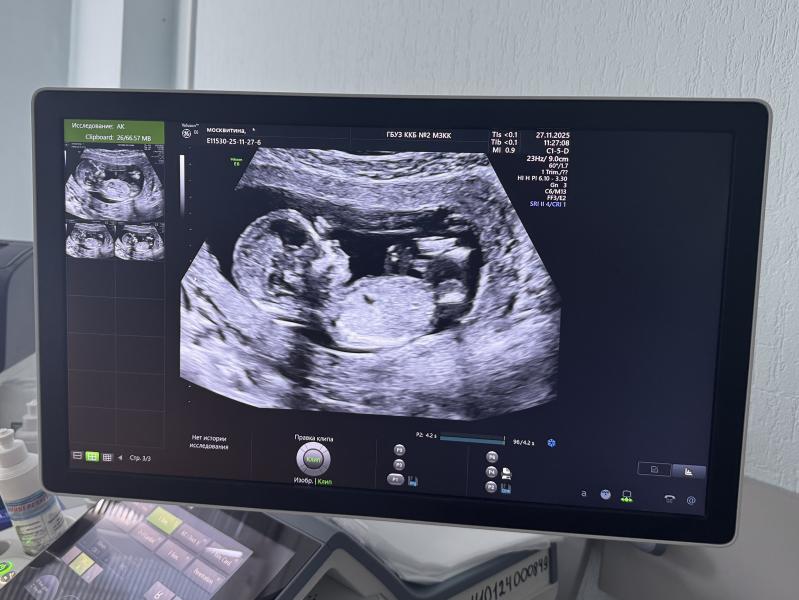

По узи сказали - будет мальчик.

Лер, это на каком сроке фотка?:)